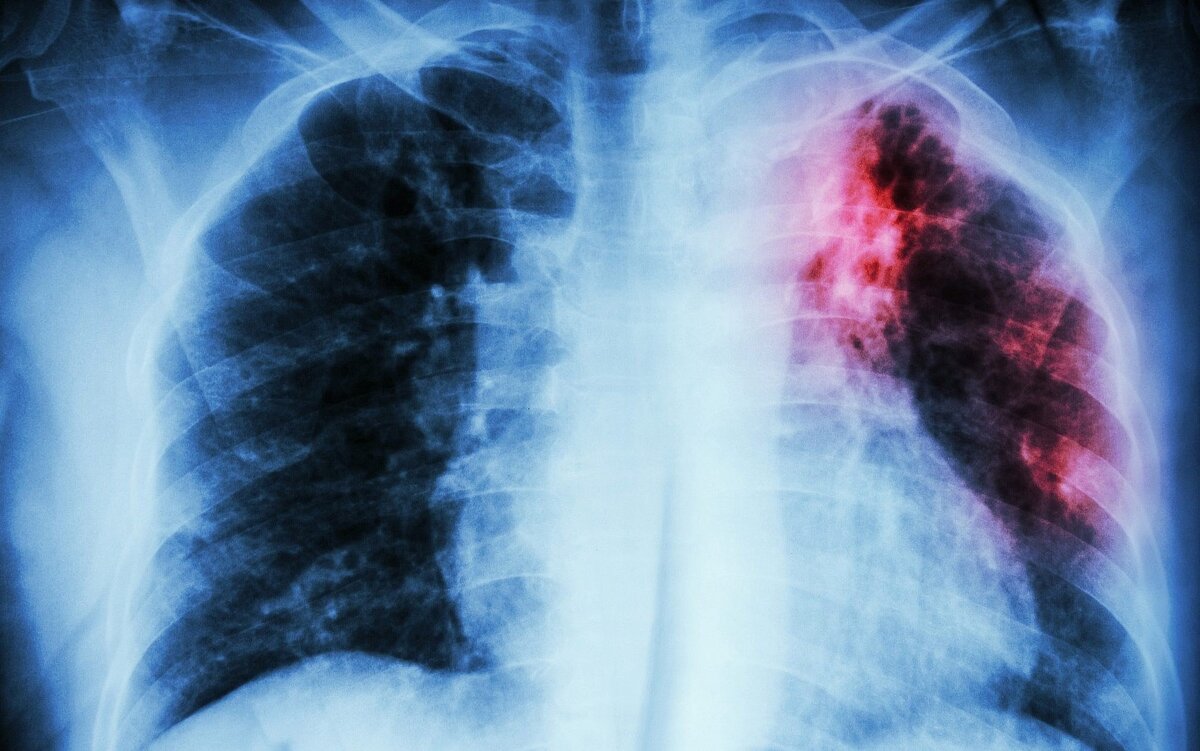

Туберкулез представляет собой известное с глубокой древности, тяжелое инфекционное заболевание, вызываемое бациллами Коха. Достаточно длительное время методы борьбы с этой болезнью не отличались эффективностью. Это в свою очередь обуславливало высокую смертность. Подобная крайне негативная картина стала причиной появления и укрепления немалого количества заблуждений и даже мифов.

Согласно актуальной статистике, на сегодня около трети населения нашей планеты заражено бациллами Коха. Однако это не свидетельствует о том, что все эти люди больны туберкулезом. Важно учитывать, что развитие патологических процессов фиксируется только в 5-7% случаев заражения рассматриваемыми микобактериями. Ключевой момент заключается в нормальном функционировании иммунной системы, которая способна эффективно контролировать возбудителей болезни и предотвращать нанесение вреда организму.

При ослаблении иммунитета бацилла сразу же получается шанс на активное размножение и начинает разрушать ткани, параллельно отравляя организм человека продуктами жизнедеятельности. Благоприятные условия для развития туберкулеза обеспечивают:

• Туберкулез – это исключительно легочная патология. Здесь стоит отметить, что в 95% случаев бацилла поражает именно органы дыхания. В остальных 5% могут пострадать ЦНС, лимфоузлы, органы зрения, суставы, костная ткань, мочеполовая система, ЖКТ и даже кожные покровы.